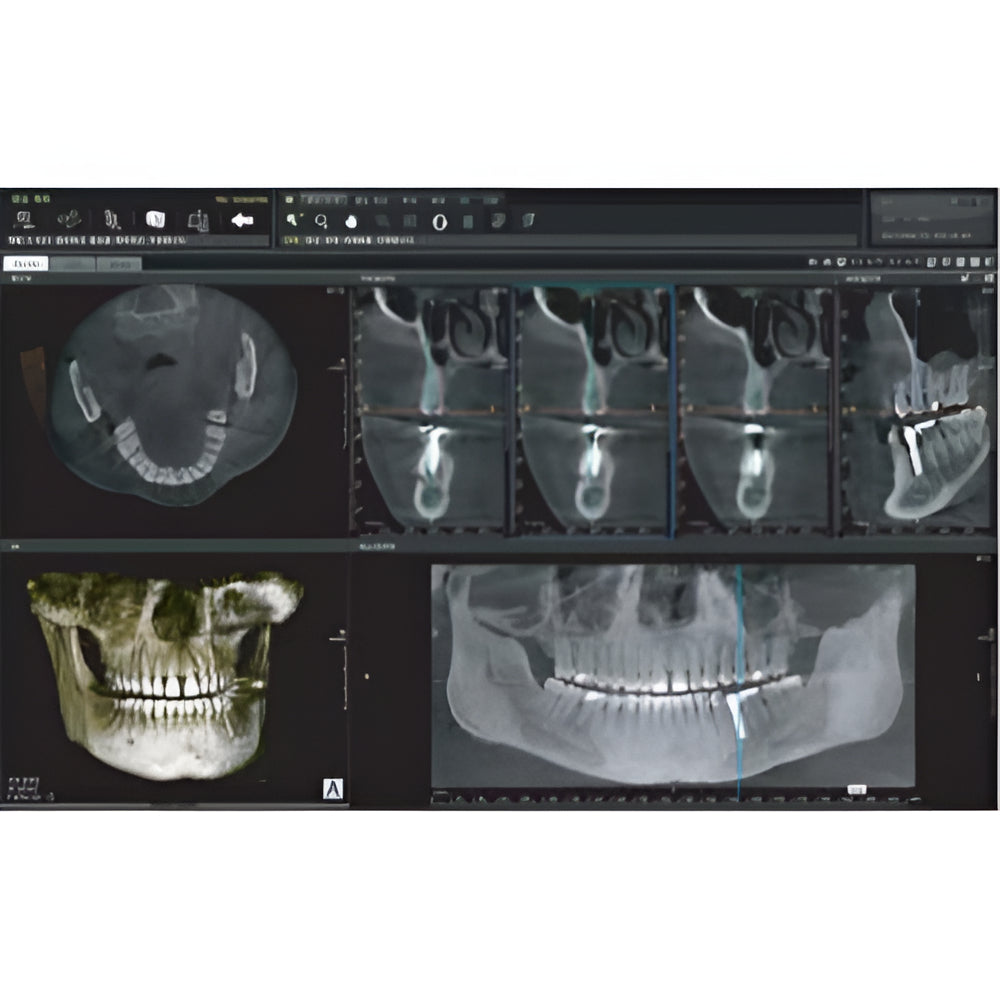

Genoray Papaya Plus Pan + CBCT (14x14 FOV)

Genoray Papaya Plus Pan + CBCT (14x14 FOV)

Papaya uses the CdTe sensor, which improves image quality while keeping radiation exposure to a minimum. The CdTe (Cadimium telluride) sensor overcomes the limitations of a CMOS sensor to always produce high quality images.

- 3D imaging software

- Field Of View: 4x5, 7x7, 8x8, 14x8, 14x14